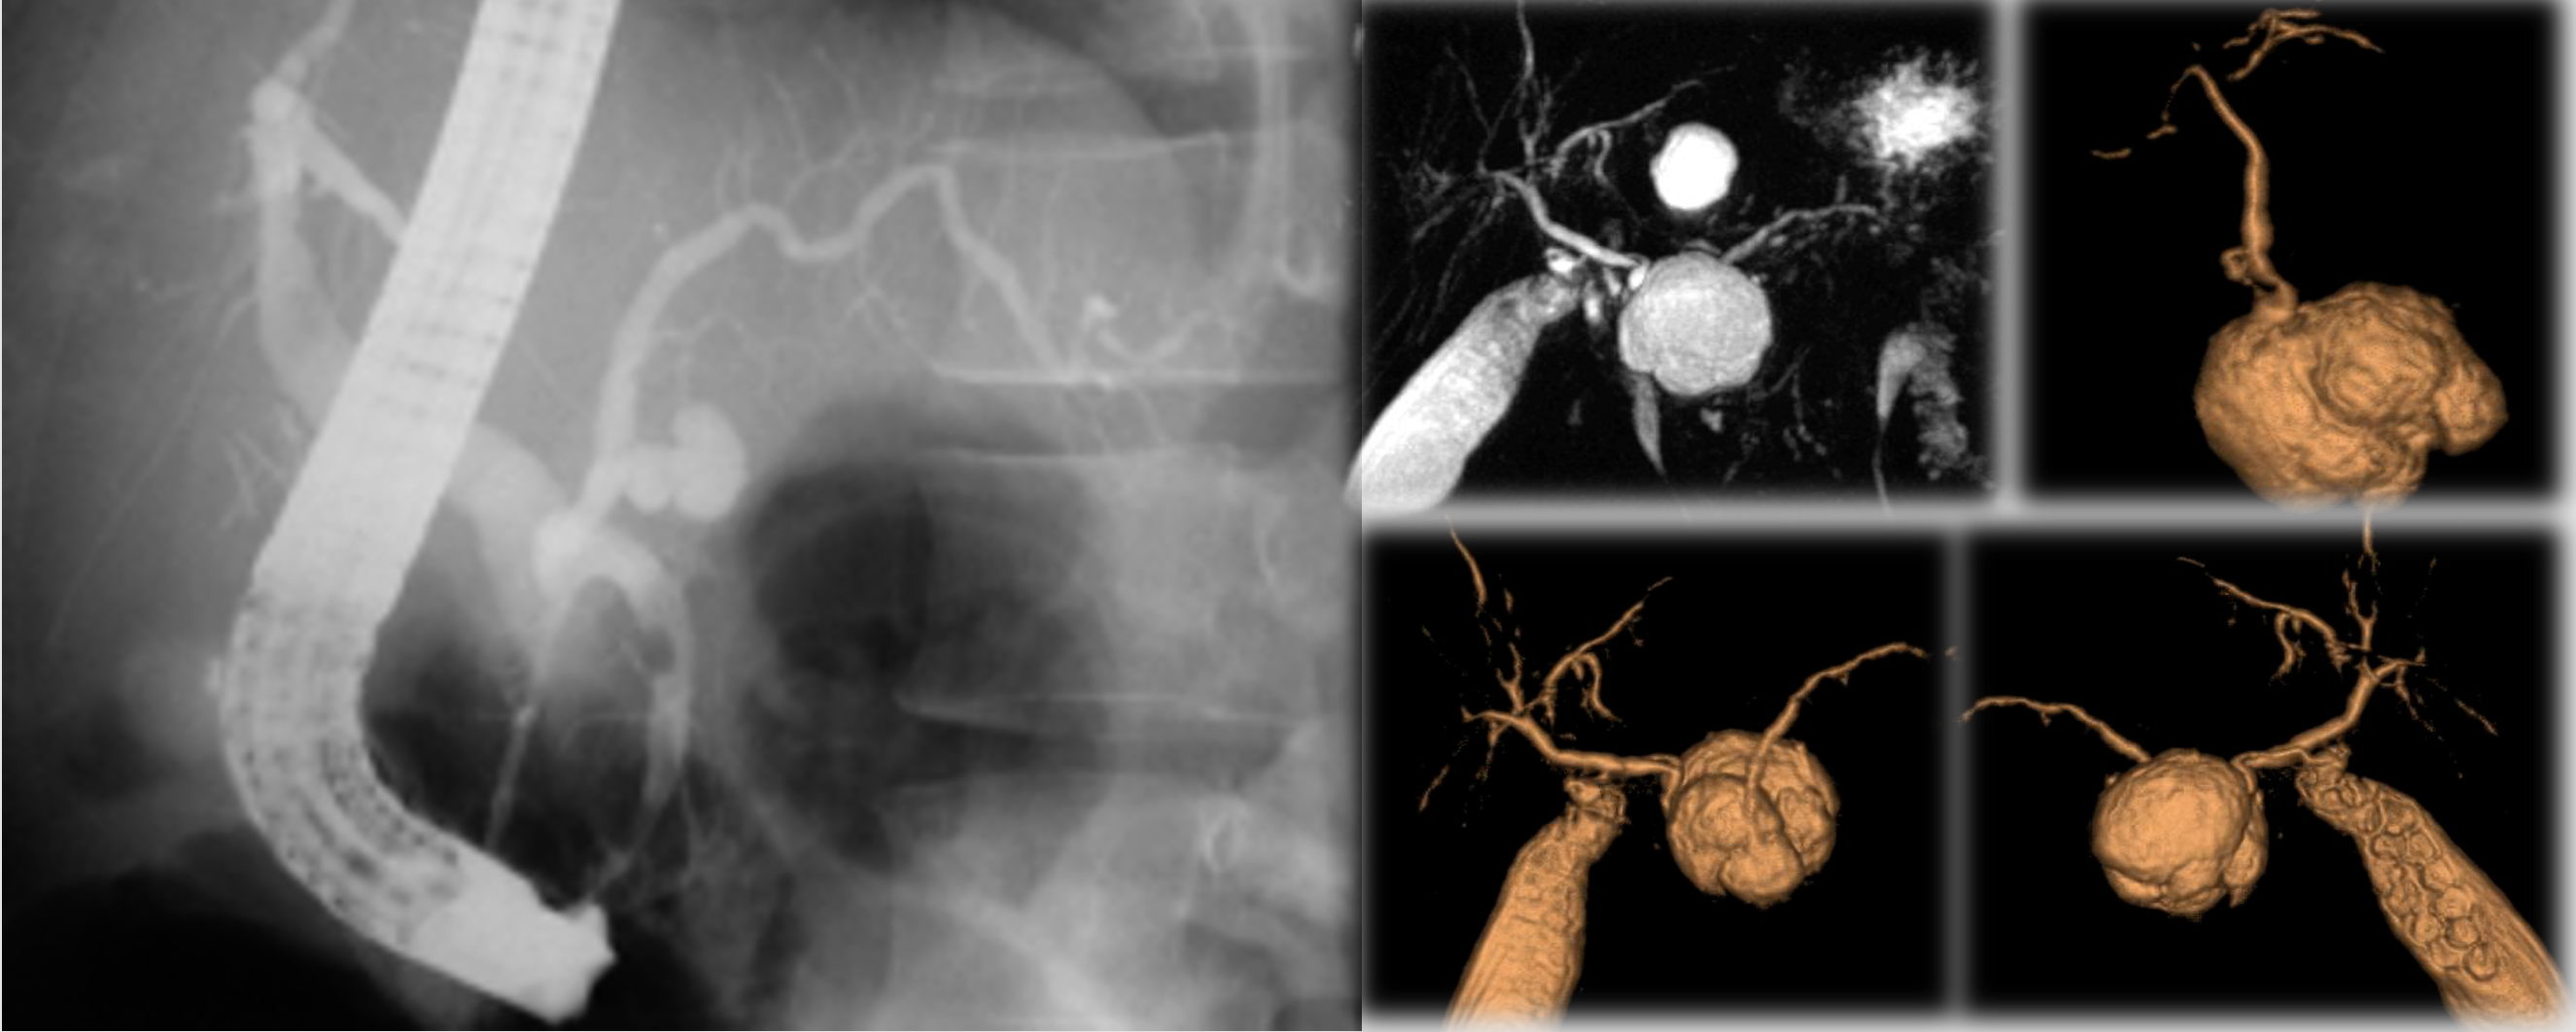

Intraductal Papillary Mucinous Tumor (IPMT)

Occurs in four forms: Y

- Main pancreatic duct: (1) Segmental (NS) |(2) Diffuse.

- Branch duct: (3) Macrocystic | (4) Microcystic.

IPMT of the MPD

- Segmental or diffuse.

- Incidence M=F, Age: 6th decade.

- Radiologic features mimic chronic pancreatitis or chronic obstructive pancreatitis.

- ERCP remains the imaging modality of choice for diagnosis.

- Contain mucinous fluid which is sometimes extruding from the ampulla of Vater.